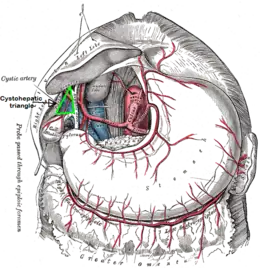

The cystohepatic triangle (or hepatobiliary triangle or Calot's triangle) is an anatomic space bordered by the cystic duct inferiorly, the common hepatic duct medially, and the inferior surface of the liver superiorly.

The cystic artery lies within the hepatobiliary triangle. The triangle is used to locate the cystic artery during a laparoscopic cholecystectomy.

The hepatobiliary triangle is the area bounded by the:

- cystic duct inferiorly[1][2]

- common hepatic duct medially[1][2]

- inferior margin of the liver superiorly[1][2]

The triangle contains: adipose and connective tissue, lymphatic vessels and the cystic lymph node, autonomic nerves, (usually) cystic artery, and (sometimes) an accessory cystic duct.[3] The right hepatic artery may also pass through the hepatobiliary triangle.[2]

The anatomy and variant anatomy of this region is important during gallbladder removal to prevent iatrogenic injury to the common hepatic duct, bile duct, or right hepatic artery.[3]

The cystic artery lies within the hepatobiliary triangle, which is used to locate it during a laparoscopic cholecystectomy.[4][5] It may also contain an accessory right hepatic artery or an anomalous sectoral bile ducts. As a result, dissection in the triangle of Calot is ill-advised until the lateral-most structures have been cleared and identification of the cystic duct is definitive. According to SESAP 12 (produced and distributed by the American College of Surgeons) dissection in the triangle of Calot is the most common cause of common bile duct injuries.

Another name used to refer to the hepatobiliary triangle is Calot's triangle, after Jean-François Calot.[6][7] Calot's original description of the triangle in 1891 included the cystic duct, the common hepatic duct, and the cystic artery (not the inferior border of the liver as is commonly believed).[4]